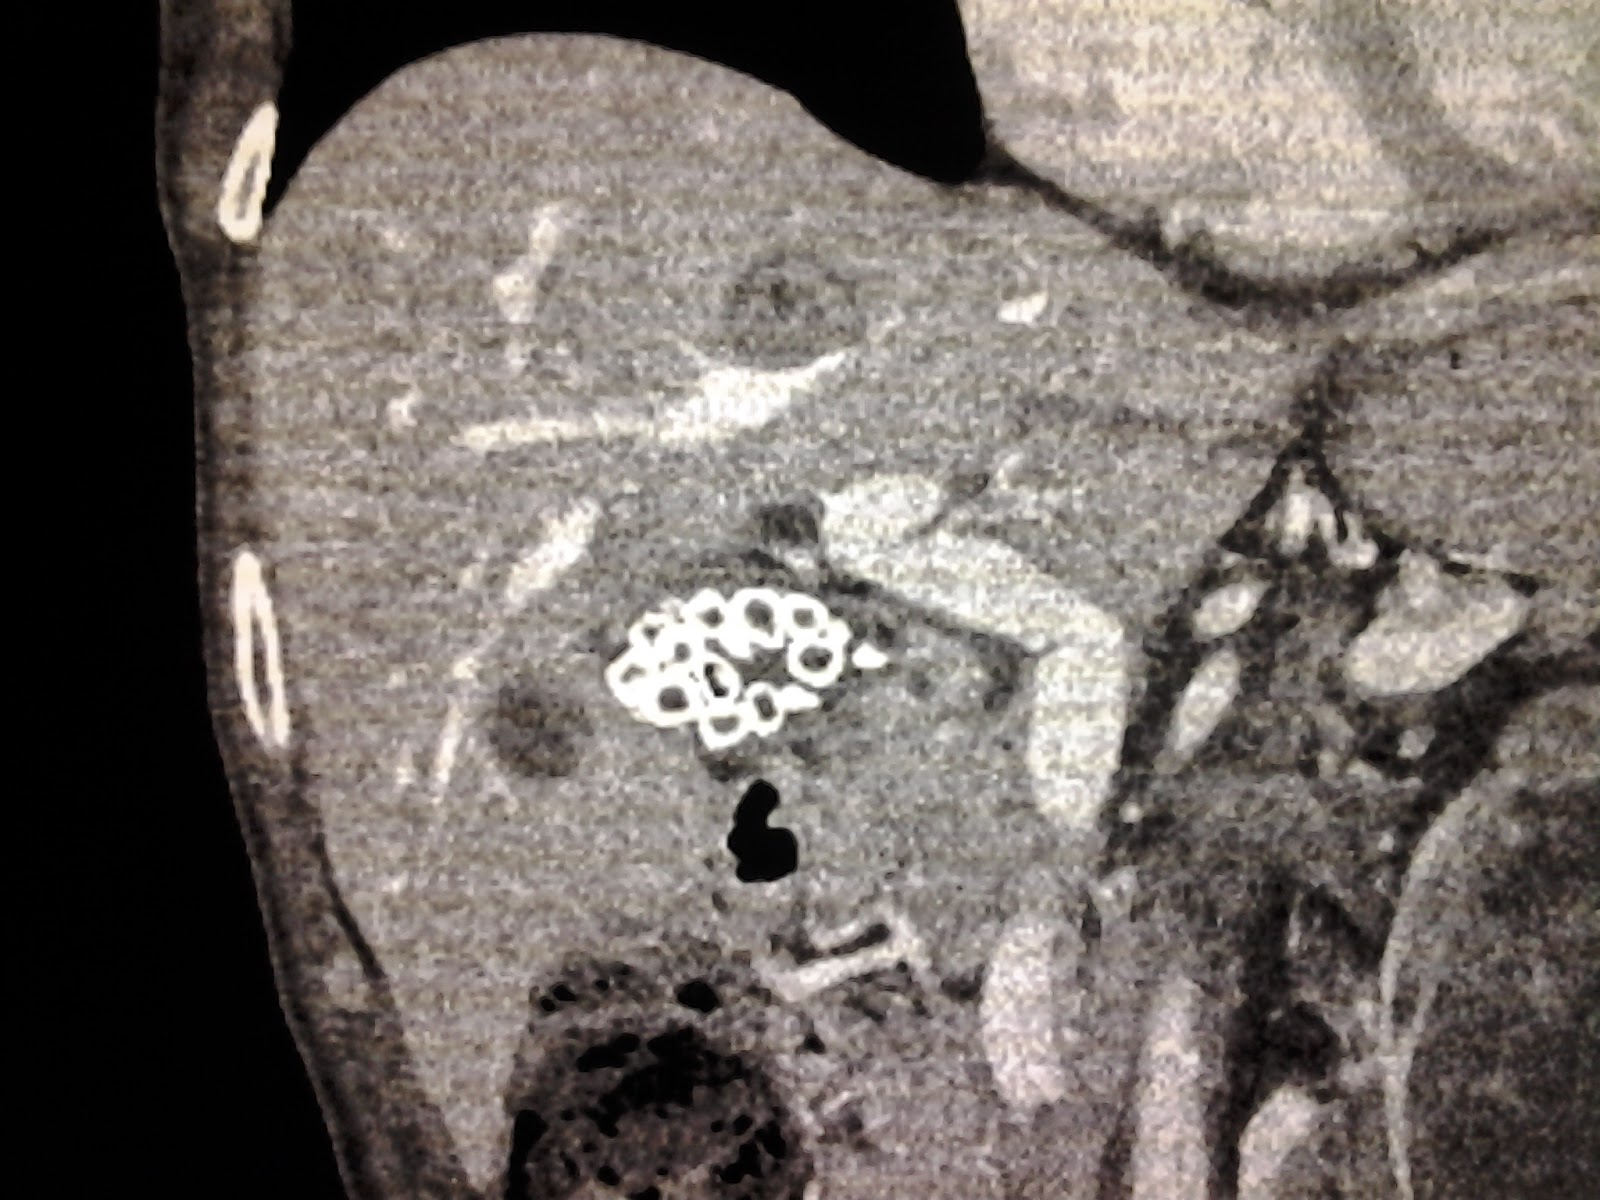

Winding Spiral Case Weekend Review Splenunculi & Peanut Butter Peanut Butter After Gallbladder Removal E to help you digest the fat. Try eating smaller, more frequent meals and snacks every. learn how peanut butter affects digestion after gallbladder removal and whether it is safe to eat. For these reasons, it’s very important to. It will also offer you ideas about how to modify your diet to avoid foods that may cause trouble while. Peanut Butter After Gallbladder Removal.